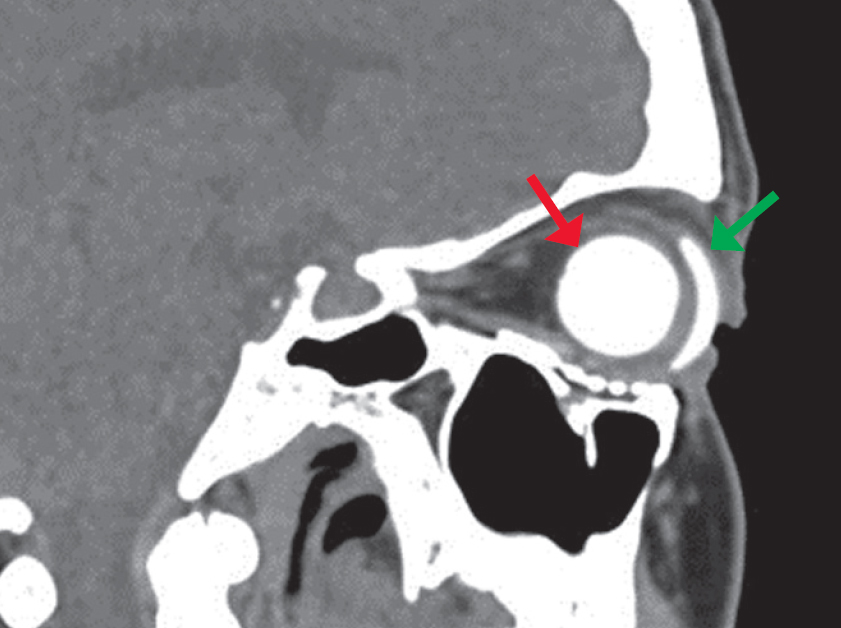

Fig. 17. MSCT of the orbit, axial section, soft tissue reconstruction mode. The state after endoprosthesis installation after evisceration of the right globe. In the anterior part of the right orbit, a centrally located endoprosthesis is visualized (red arrow), round in shape, with homogeneous structure, 20 mm in diameter, with an average density of +372 HU, no additional inclusions in the area of the prosthesis were identified, the endoprosthesis capsule with clear, even contours is visualized in the anterior part. An external cosmetic prosthesis is adjacent to the front surface of the endoprosthesis (green arrow). The orbital floor of the right orbit is reconstructed with a mesh implant, without any signs of bone-destructive changes

Рис. 17. МСКТ орбиты, аксиальный срез, режим мягкотканной реконструкции. Состояние после эндопротезирования правого глазного яблока после эвисцерации. В переднем отделе правой орбиты визуализируется центрально расположенный эндопротез (красная стрелка), округлой формы, однородной структуры, диаметром 20 мм, средней плотностью +372 HU, дополнительных включений в области протеза не выявлено, в передней части визуализируется капсула эндопротеза с чёткими ровными контурами. К передней поверхности эндопротеза прилежит наружный косметический протез (зелёная стрелка). Нижняя стенка правой орбиты протезирована сетчатым имплантатом, без признаков костно-деструктивных изменений

Fig. 21. Eyeball endoprosthetics: a — schematic representation of orbital structures (Э — endoprosthesis, K — nerve stump, Н — external cosmetic prosthesis); b — MSCT of the orbit, sagittal reconstruction, soft tissue window mode, with intravenous contrast, state after endoprosthetics of the left globe. In the anterior part of the left orbit, a centrally located endoprosthesis is visualized (red arrow), round in shape, with homogeneous structure, of 20 mm in diameter, average density of –33 HU, no additional inclusions in the area of the prosthesis were identified, in the anterior part an endoprosthesis capsule with clear, even contours is visualized. An external cosmetic prosthesis (green arrow) is adjacent to the front surface of the endoprosthesis, with the presence of air vacuoles between them

Рис. 21. Эндопротезирование глазного яблока: a — схематическое изображение структур орбиты (Э — эндопротез, К — культя нерва, Н — наружный косметический протез; b — МСКТ орбит, сагиттальный срез, режим мягкотканного окна, с внутривенным контрастированием, состояние после эндопротезирования левого глазного яблока. В переднем отделе левой орбиты визуализируется центрально расположенный эндопротез (красная стрелка), округлой формы, однородной структуры, диаметром 20 мм, средней плотностью –33 HU, дополнительных включений в области протеза не выявлено, в передней части визуализируется капсула эндопротеза с чёткими ровными контурами. К передней поверхности эндопротеза (к опорной культе) прилежит наружный косметический протез (зелёная стрелка), с наличием вакуолей воздуха между ними